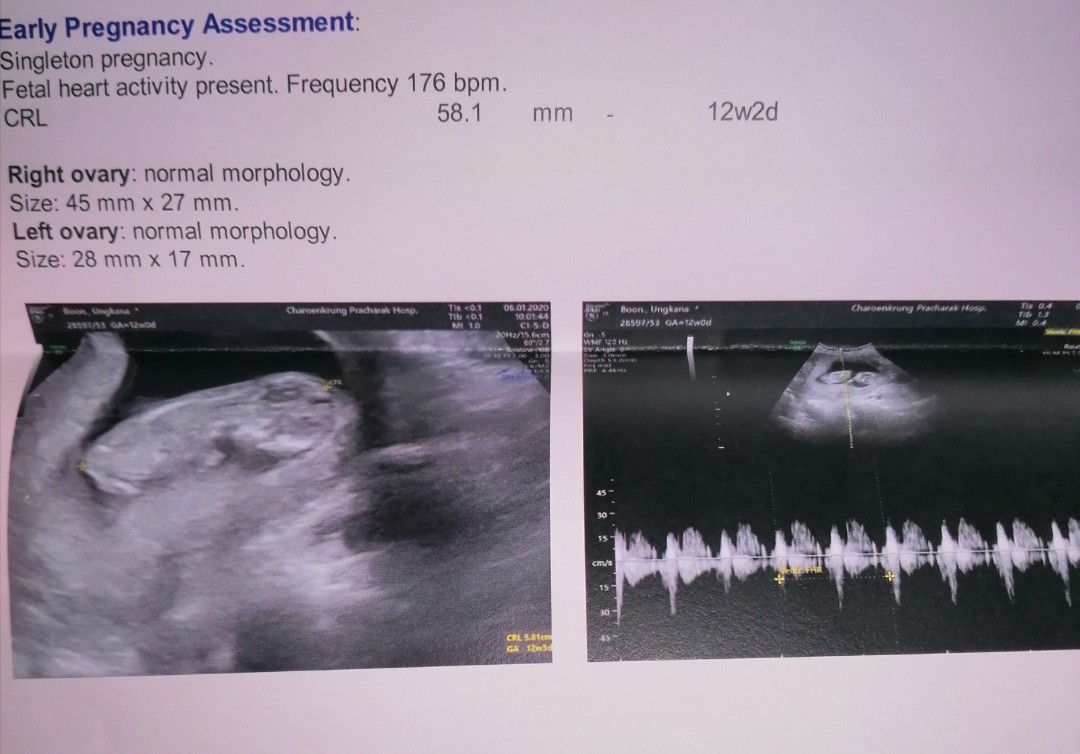

12week2day.